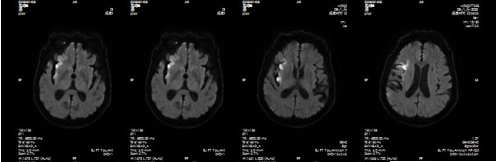

结论:左侧大脑半球多发梗死灶,T2 flair高信号区域小,左侧颈内-大脑中闭塞,T1 flair提示小出血灶后通过CT排除出血,初步确认为梗死/坏死。

病历夹什么径技·第151期|串联营病历夹:京广连营_https://www.jmylbn.com_新闻资讯_第26张

病历夹什么径技·第151期|串联营病历夹:京广连营_https://www.jmylbn.com_新闻资讯_第27张

病历夹什么径技·第151期|串联营病历夹:京广连营_https://www.jmylbn.com_新闻资讯_第28张

病历夹什么径技·第151期|串联营病历夹:京广连营_https://www.jmylbn.com_新闻资讯_第29张

<<滑动查看下一张图片>>

• 首先放置1型弓,排除左侧颈源系统嫌疑,右侧颈源系统由右向左通过软脑膜部分代偿,后循环向前循环少许代偿。

• 左颈总造影显示C1远端逆流,提示串联病变。

• 输送微导丝与中间管,中间管抽吸后在C7段冒烟(A),遂进行微导管造影(B)

• 将中间管送至AB段进行抽吸,中间管只能在M1中段抽吸。

• 抽吸后正位造影显示颅内操作效果良好。

• 输送保护伞,保护伞下撤指引造影侧位C1狭窄。

• 4*30球囊预扩后,将7*40 Carotid Wallstent支架植入后正位,血流得到明显恢复。